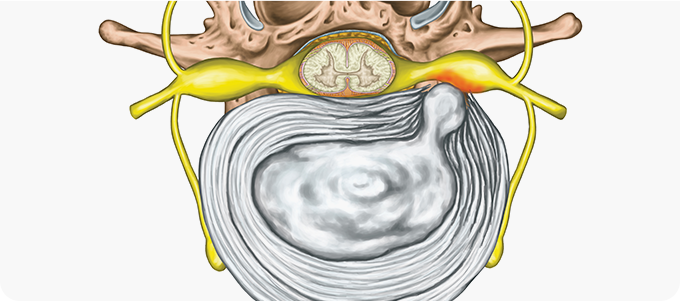

척추관 협착증

척추관 협착증 관련 이미지

• 허리를 앞으로 굽힐 때는 별다른 통증이 없지만 뒤로 젖히면 통증이 심해진다.

• 누워 있다가 일어나기는 힘들지만 일단 움직이면 허리가 조금씩 부드러워 진다.

• 오래 걸으면 다리가 저려 잠시 주저 앉았다 걸으면 편하다.

• 누워서 다리를 들어 올리는 동작에 무리가 없다.